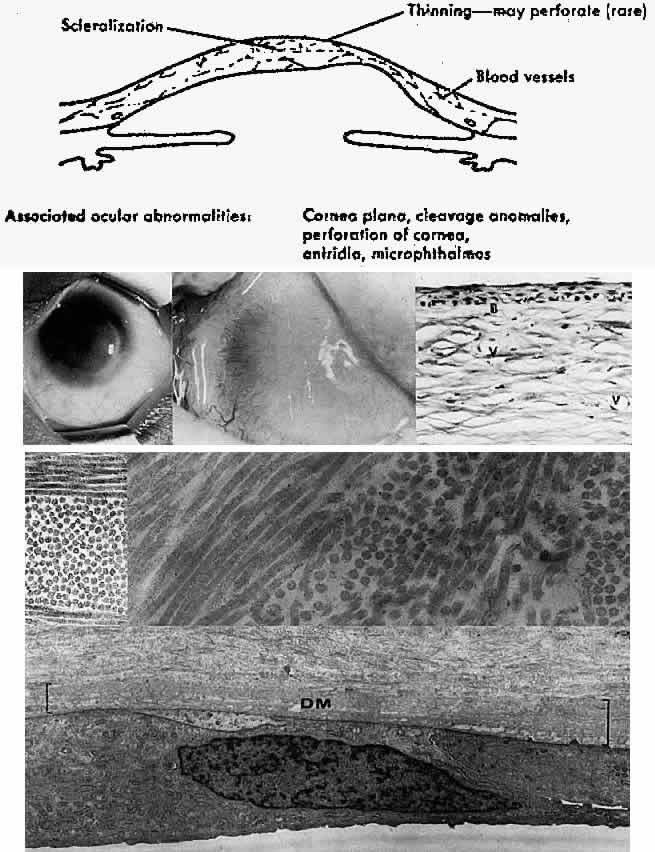

endothelial dystrophy. Exp Eye Res 21:125, 1975 23. Waring GO III, Rodrigues MM, Laibson PR: Anterior chamber cleavage syndrome: A stepladder classification. Surv Ophthalmol 20:3, 1975 24. Axenfeld T: Embryotoxon corneae posterius. Dtsch Ophthalmol Gesamte 42:301, 1920 25. Sugar HS: Juvenile glaucoma with Axenfeld's syndrome: A histologic report. Am J Ophthalmol 59:1012, 1965 26. Dark AJ, Kirkham TH: Congenital corneal opacities in a patient with Rieger's anomaly and